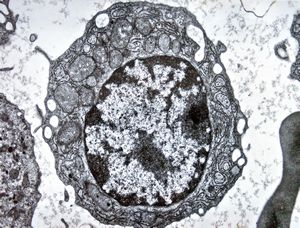

M,38y. | blood, myeloid leukemia

M,80y. | blood - myeloid leukemia